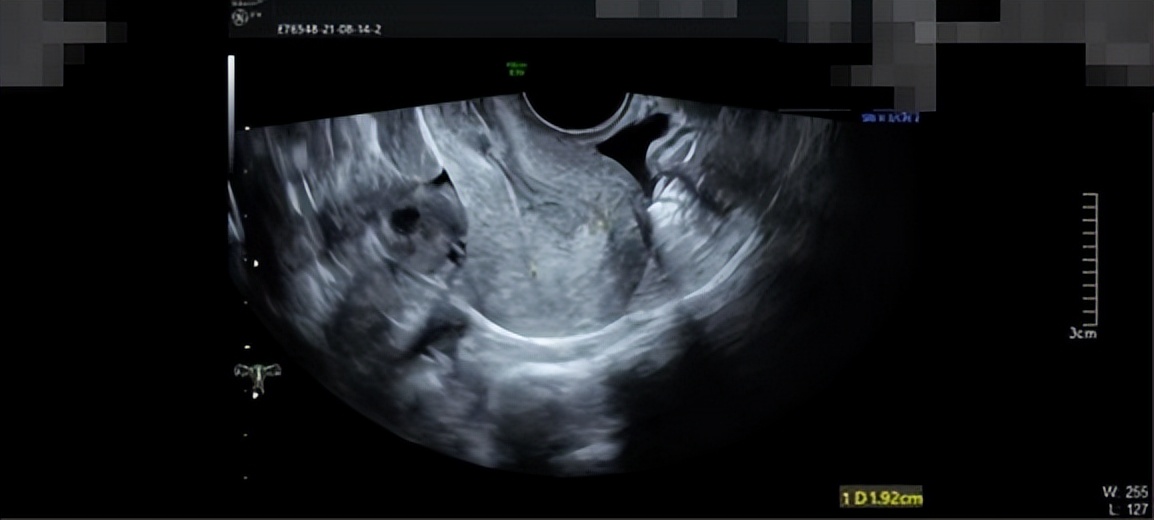

周女士十分焦虑,她问我:“医生,我之前流产过一次,然后现在我又一直出血,我以后不会不能怀孕了吧?我还没有结婚,我还想生个孩子,医生,你一定要帮帮我”我对周女士说:“我们会尽力的”我的内心能够感受到周女士迫切的心情,我想子宫对一个未孕女子的意义重大,我们作为医者,一定要从患者的切身角度去维护好患者最大的意愿。我查阅周女士的病历了解到,周女士在2021年8月初的时候就诊医院B超检查子宫,超声提示内膜厚1.8cm(双层),回声不均,考虑子宫内膜厚,如图1所示,当时给予黄体酮口服12天,情况缓解。在2021年9月,月经第5天时复查,超声提示内膜增厚1.29cm(双层),回声不均,宫腔内见1.1*0.8*0.6cm稍低回声,内见星点状血流,息肉?粘肌?如图2所示。

图1.腹部B超结果显示